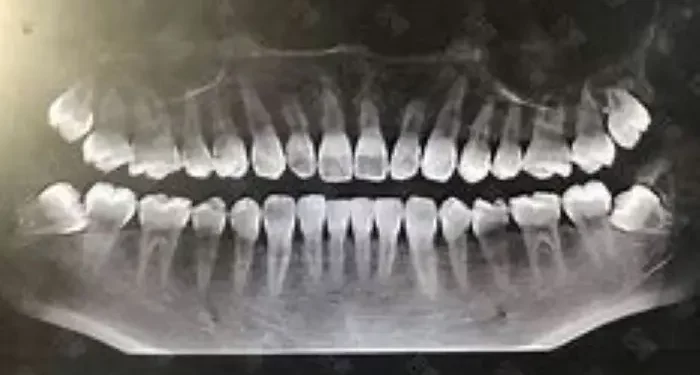

X-Rays: Dental X-rays help identify areas of decay that may not be visible during a physical examination. They can reveal the extent of decay, including whether it has reached the pulp.